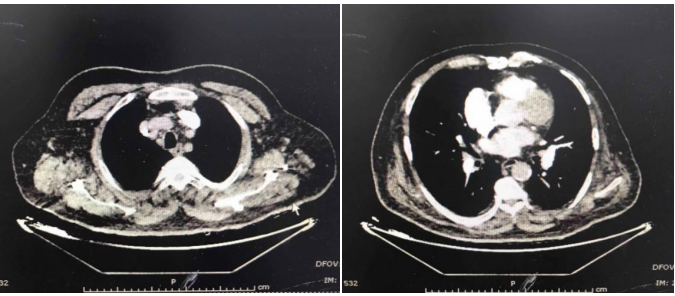

患者行冠脉造影:冠脉可见钙化影 , 右优势性冠脉;LM斑块 , 末端狭窄20%-30% , LAD斑块 , LCX纤细斑块 , 中段闭塞;RCA斑块 , 中段狭窄90% , 于RCA植入FIREBIRD2 4.0×23 mm支架1枚 , TIMI分级 。

图2 , 左图:右冠脉支架植入前;右图:右冠脉支架植入后